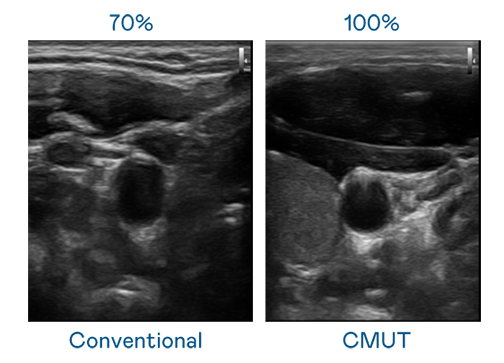

CMUT 技術是一種用電容式微機電元件來產生超音波訊號的技術。與傳統 PZT 壓電式技術相比,CMUT 頻寬增加 30%,更寬頻的超音波訊號讓影像解析度大幅提升,是實現高影像品質醫療超音波掃描、促進精準醫療發展的關鍵技術。

大頻寬帶來超清晰影像

超音波影像的解析度高低,首先取決於探頭能發出的訊號頻寬。z6.com CMUT 可提供高清晰的超音波訊號,提供高頻寬、高靈敏度、影像紋理細節更高的超音波影像,協助醫護人員縮短影像判讀時間及利用精準的醫療影像進行診斷。